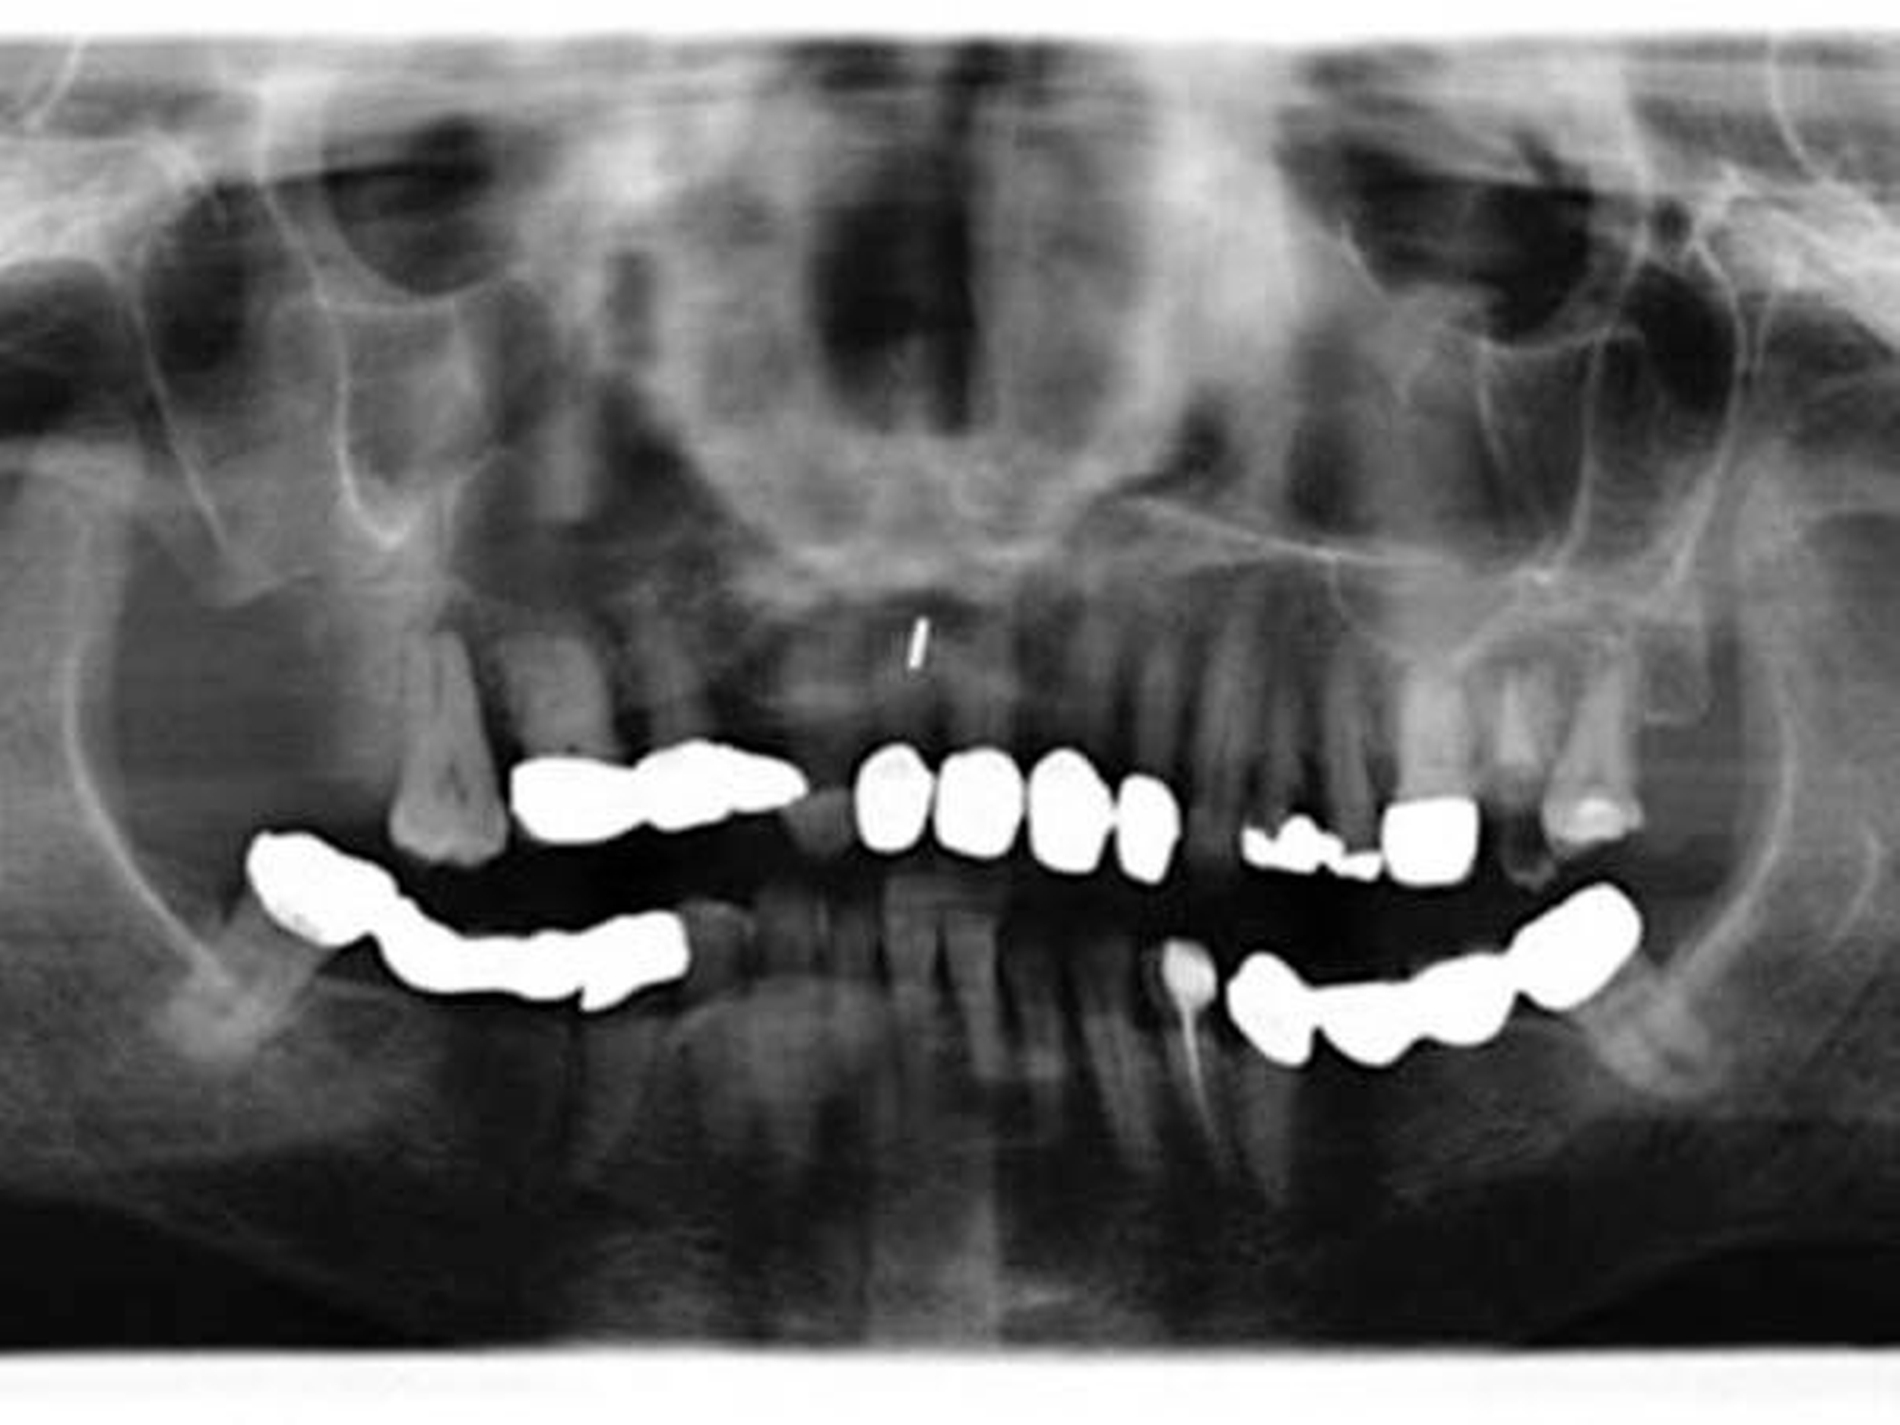

Nach Anlage eines temporären Tracheostomas und Neck Dissection Level I-III rechts erfolgte die Tumorexzision von transoral via midfacial degloving. So konnte auf eine extraorale Erweiterung des Zugangswegs nach Weber-Dieffenbach verzichtet werden.

Insgesamt wurden die Zähne 15 bis 17 und 26 bis 28 mit entfernt, und die Defektausdehnung umfasste somit eine distale Zweidrittel-Maxillektomie, also rechts ab Zahn 14 und links ab Zahn 26 nach distal mit Resektion bis in die Fossa pterygopalatina.

Bei Ausgang des Tumors von den kleinen Speicheldrüsen im Bereich des harten Gaumens und in Zusammenschau mit den üblichen Staging-Untersuchungen ergibt sich folgende postoperative Tumorklassifikation [TNM 8. Auflage 2017]: pT3, pN1(1/6), M0, L0, V0, Stadium III, Differenzierungsgrad G1, R1.

In einem Resektat der Neck Dissection rechts wurde ein Lymphknoten gefunden, in dem zwei kleinherdige, beginnende und knapp über 1 mm messende gleichartige, teils papilläre Epithelproliferationen wie im Tumorhauptresektat zu sehen waren. Dieser Befund wurde als eine initiale Tumormetastase gewertet. Einzelne Tumorformationen waren im kranialen und pterygomaxillären Nachresektat noch zu finden.